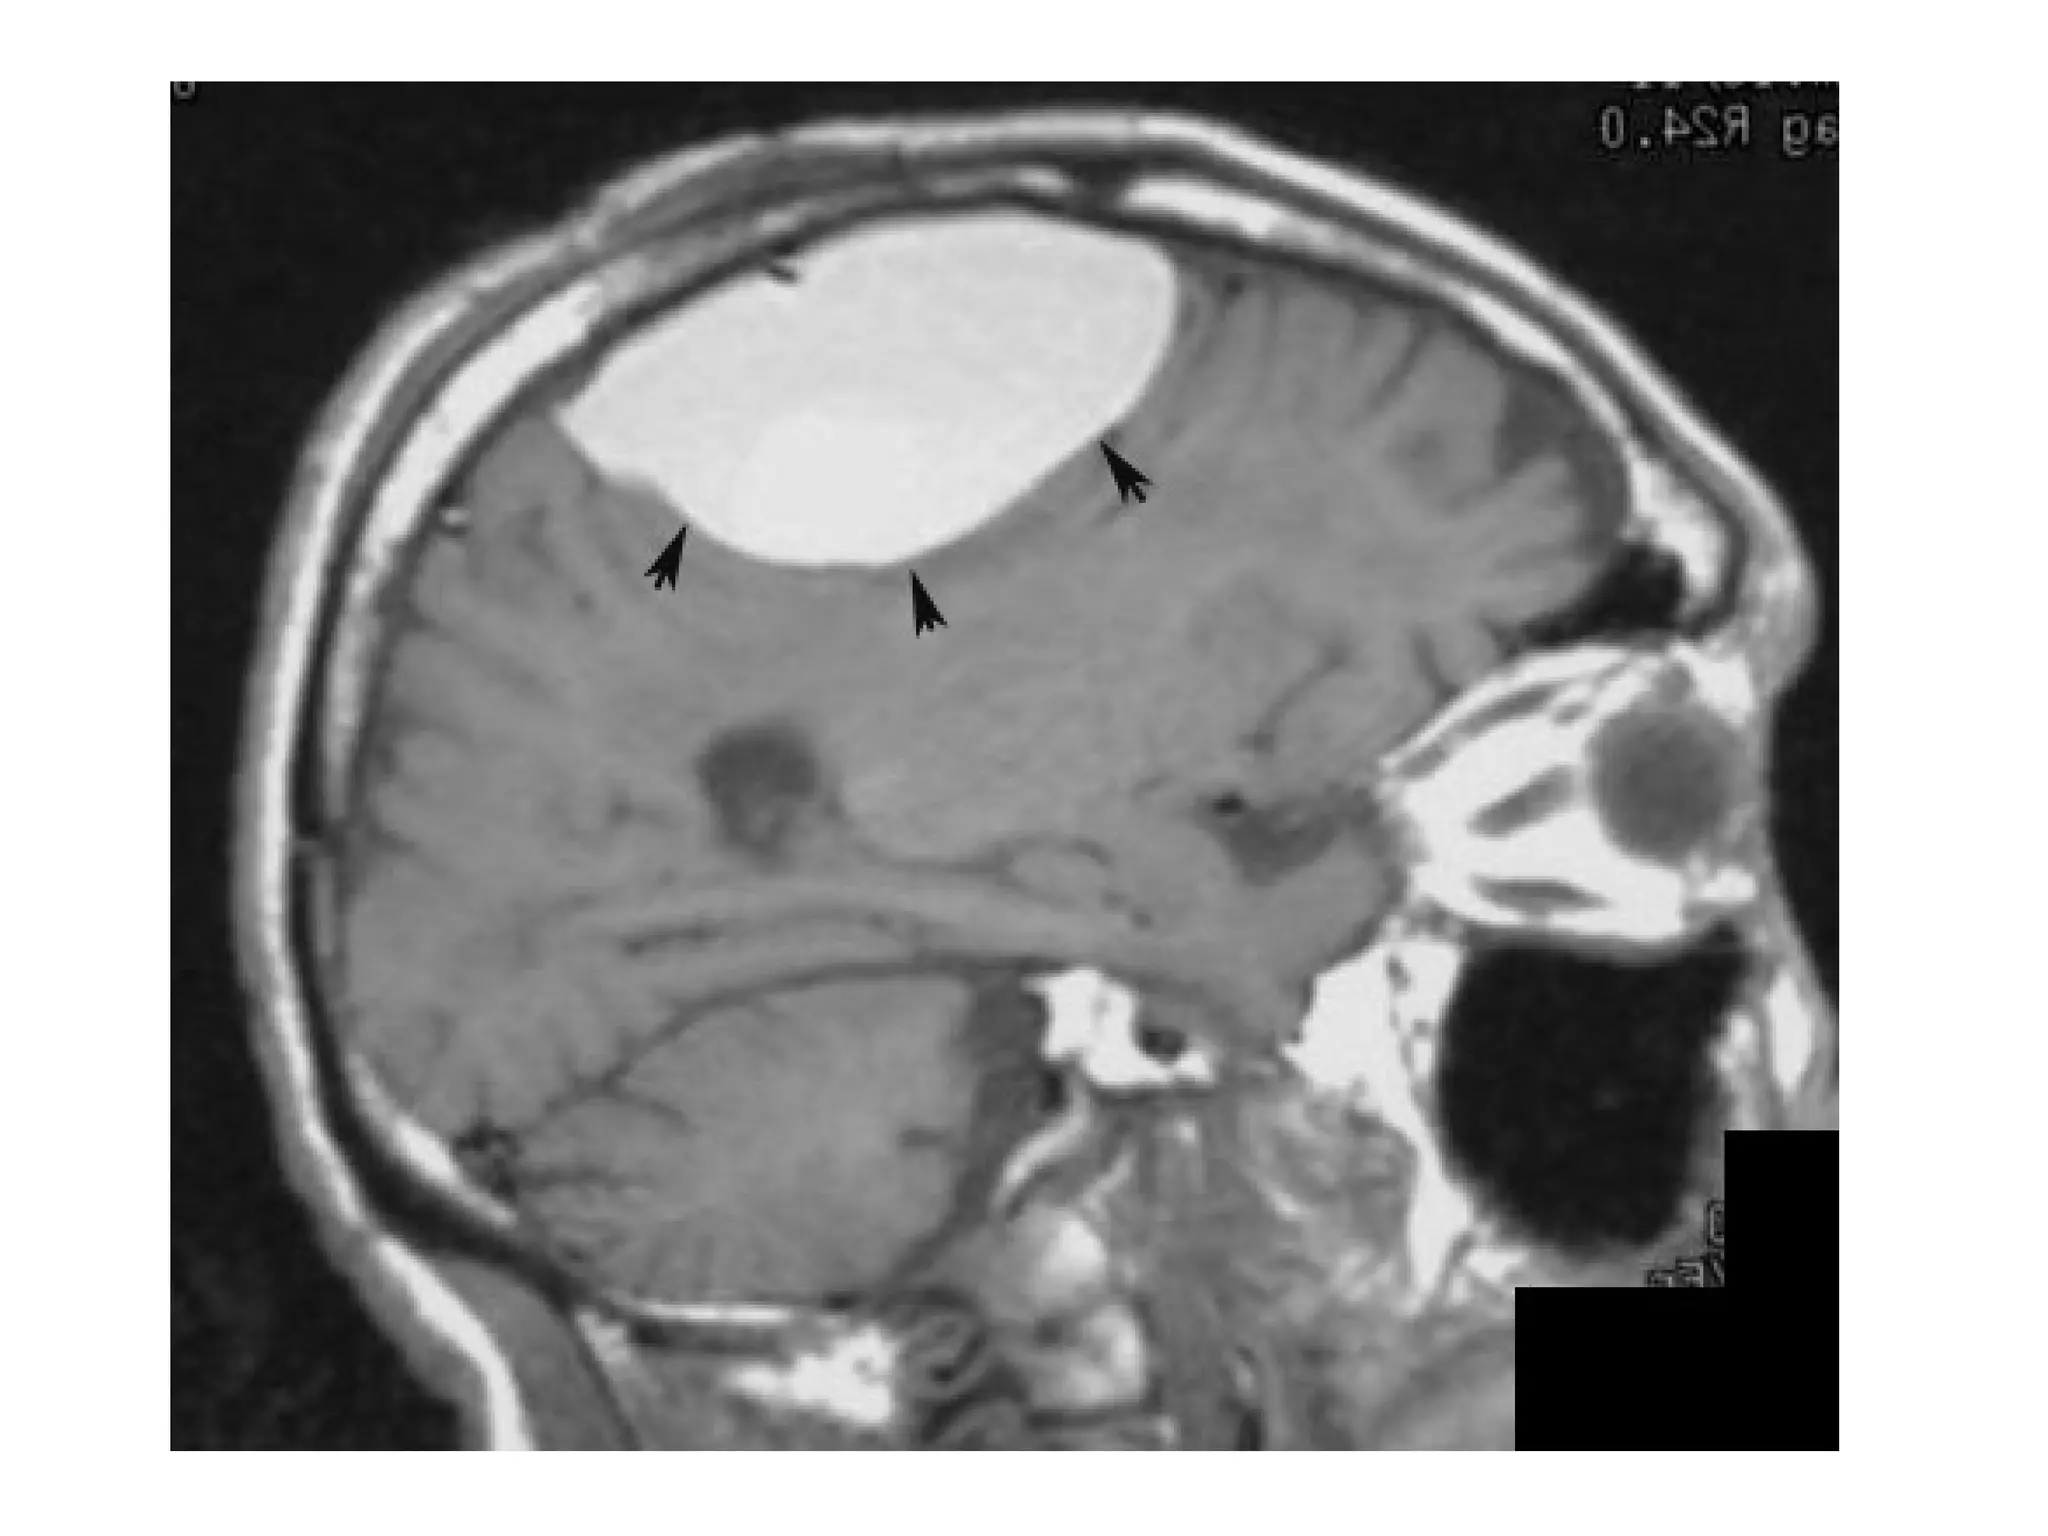

1-Straight sinus

2-Internal cerebral vein

3-ACA (A2)

4-ACA (A3)

5-Callosomarginal artery

6-Pericallosal artery

7-Corpus callosum

ACA infarction